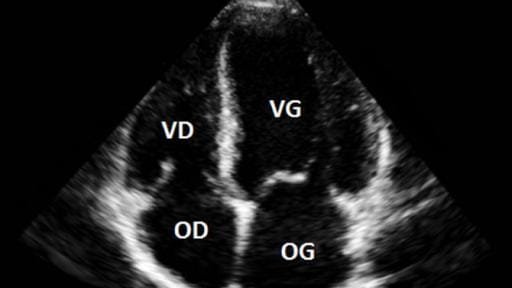

L’échocardiographie trans thoracique (ETT) est une technique d’imagerie non invasive qui utilise des ultrasons pour examiner le cœur et ses structures. C’est un outil essentiel pour diagnostiquer et surveiller diverses maladies cardiaques.